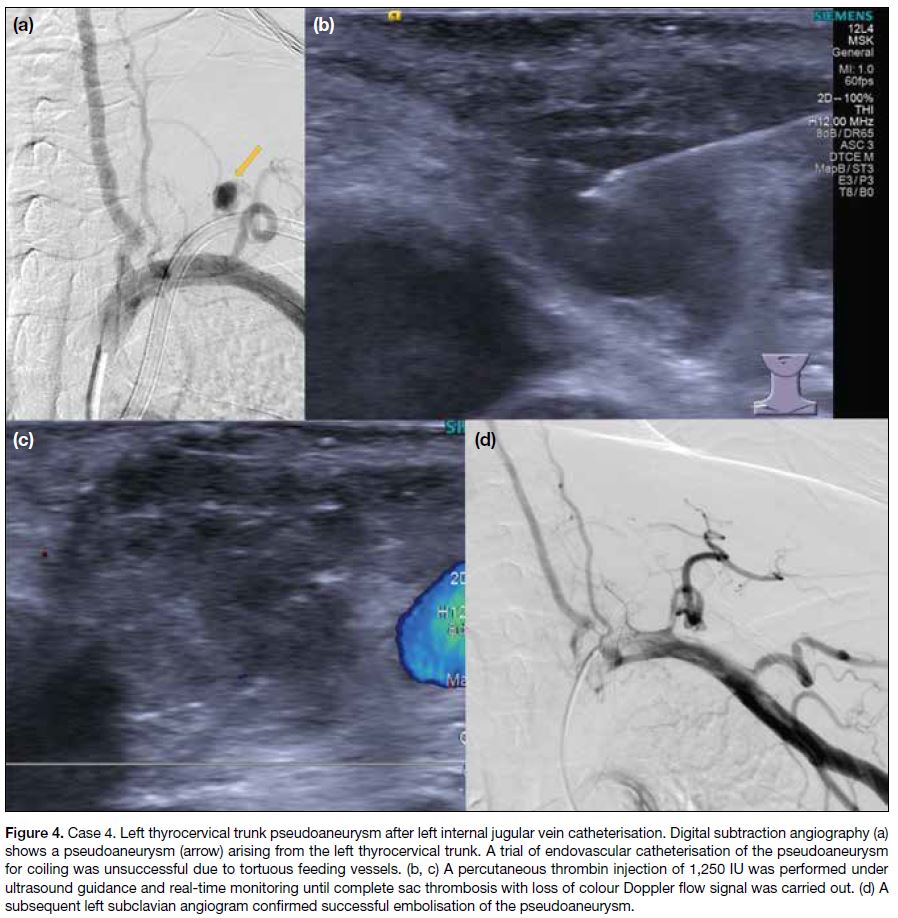

Figure 4. Case 4. Left thyrocervical trunk pseudoaneurysm after left internal jugular vein catheterisation. Digital subtraction angiography (a)

shows a pseudoaneurysm (arrow) arising from the left thyrocervical trunk. A trial of endovascular catheterisation of the pseudoaneurysm

for coiling was unsuccessful due to tortuous feeding vessels. (b and c) A percutaneous thrombin injection of 1,250 IU was performed under

ultrasound guidance and real-time monitoring until complete sac thrombosis with loss of colour Doppler flow signal was carried out. (d) A

subsequent left subclavian angiogram confirmed successful embolisation of the pseudoaneurysm.